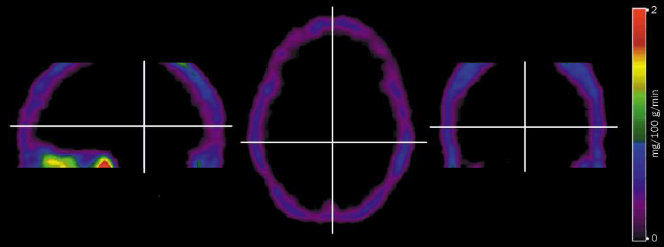

Zużycie energii: ok. 20% całkowitego zużycia tlenu i 25% zużycia glukozy, przy 2% masy całego ciała; mózg zużywa więc energię 10 razy szybciej niż inne części ciała.

zużyciu energii przez mózg ludzki:

50% energii zużywanych jest przez postsynaptyczne receptory glutaminowe,

21% na generowanie potencjałów czynnościowych,

5% na uwalnianie neurotransmiterów, a 4% na ich recycling.

75% zużywają neurony pobudzające a 25% hamujące.

Zużycie energii przez mózg gryzonia to tylko 2% całkowitej energii zużywanej przez organizm, około 9%–12% u większości naczelnych i 20% u ludzi. Kora zużywa 40% energii całego mózgu, chociaż to mniej niż 10% wszystkich neuronów (Magistretti i Allaman, 2015).